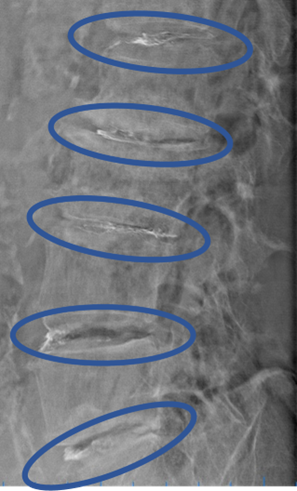

DiscoGelを入れた後の画像になります。

治療は 50分 程度で終了

回復室で休憩後、歩いて帰院されました。